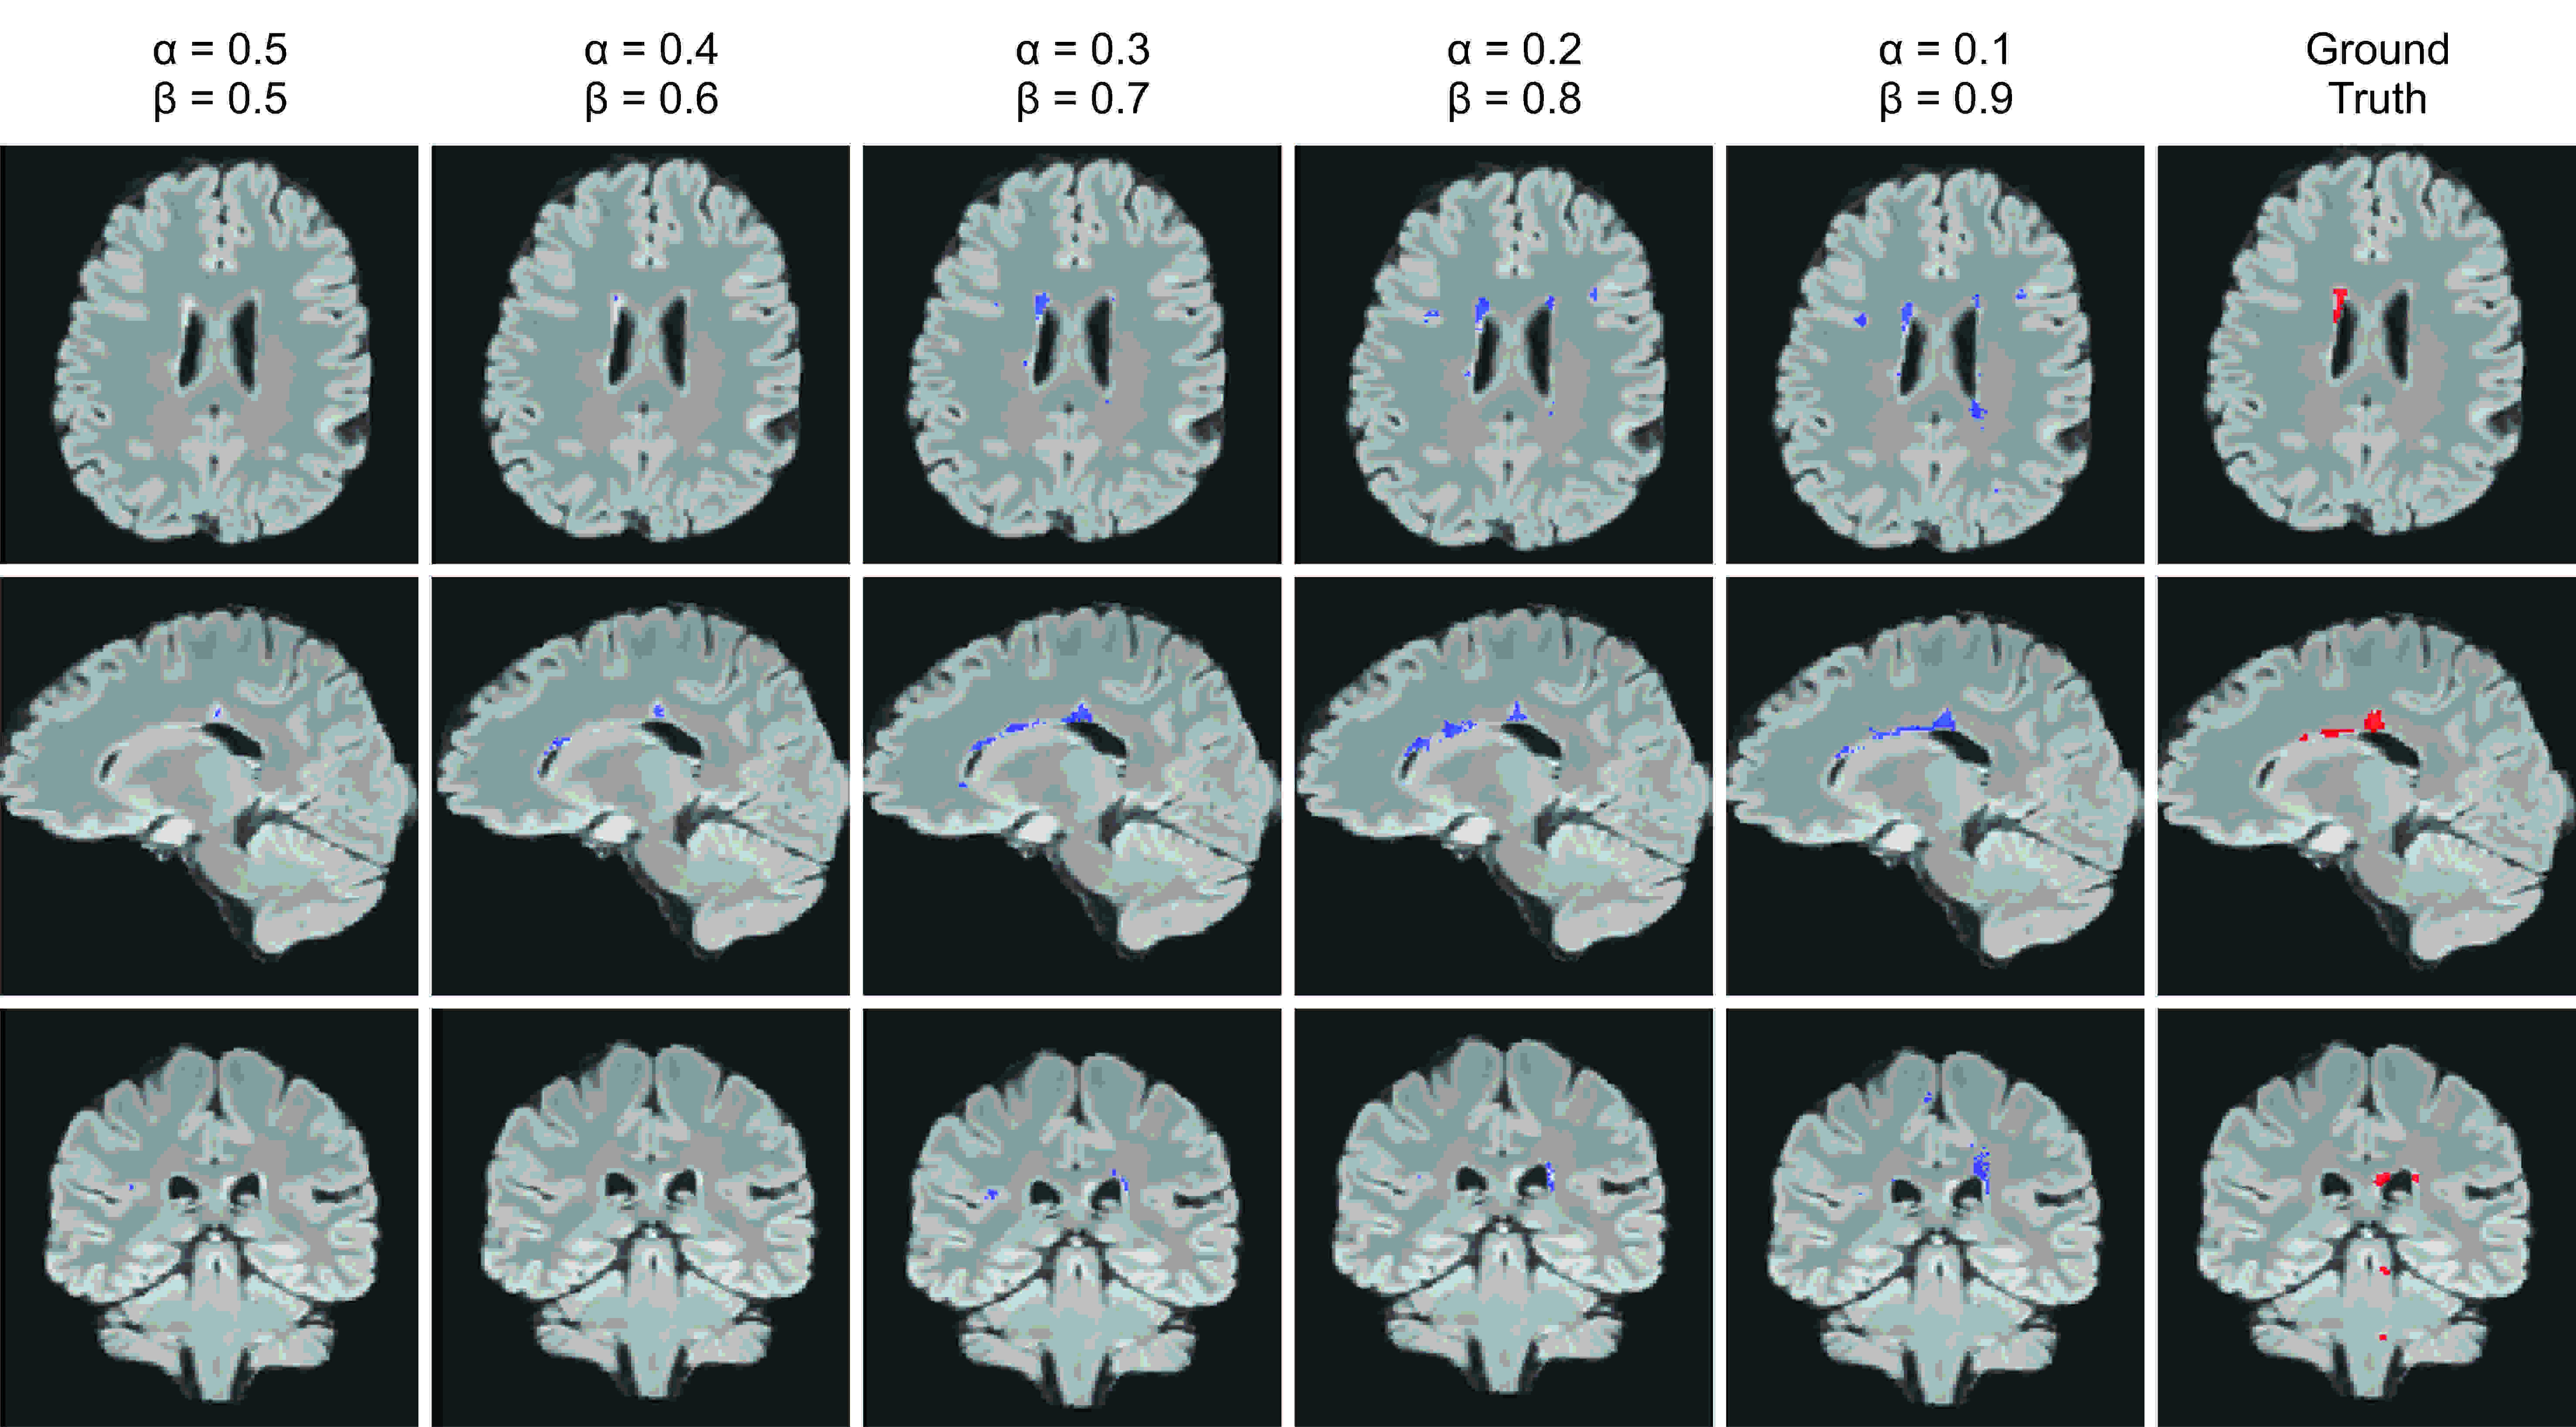

Figures 3 and 4 show the effect of different penalty magnitudes (β𝛽\betas) on segmenting a subject with high density of lesions, and a subject with very few lesions, respectively. These cases, that correspond to the PR curves shown in Figure 2(b and c), show that the best performance was achieved by using a loss function with β=0.7𝛽0.7\beta=0.7 in training. We note that the network trained with the Dice loss layer (β=0.5𝛽0.5\beta=0.5) did not detect the lesions in the case shown in Figure 4.

Refer to caption

Figure 4: The effect of different penalties on FP and FN in the Tverskey loss function on a case with extremely low density of lesions. The best results were obtained at β=0.7𝛽0.7\beta=0.7.